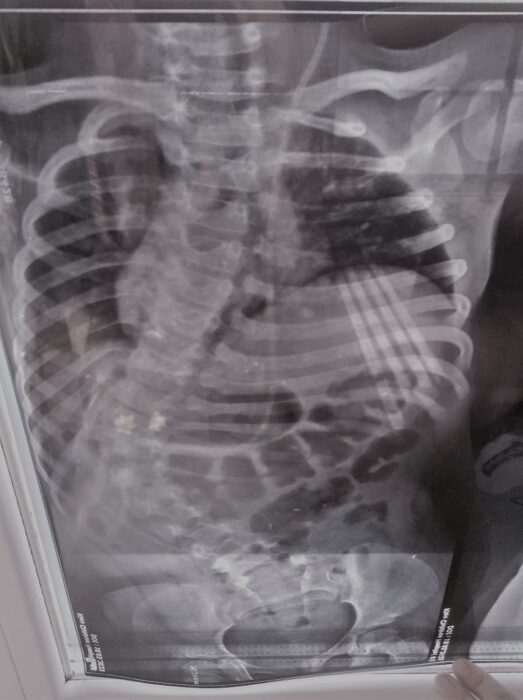

Лещинська Ліза, 5 рочків, спина-біфіда, сколіоз

300 тис.грн. Це дуже великий , але вкрай важливий збір для життя однієї маленької дівчинки. Ліза – довгоочікувана і бажана донечка, народилася с важкою вродженою вадою – розщеплення хребта. Першу операцію перенесла вже на другий день після народження. Потім – ще кілька втручань. Родина постійно займається з дитиною: курси реабілітацій, лфк, заняття вдома. Лізонька зростає дуже доброю, веселою та розумною. Але, не зважаючи на всі заняття, в дитини прогресує життєзагрожуючий сколіоз. Через викривлення хребта, стискаються и не можуть нормально зростати та функціонувати внутрішні органи: серце, легені, печінка…